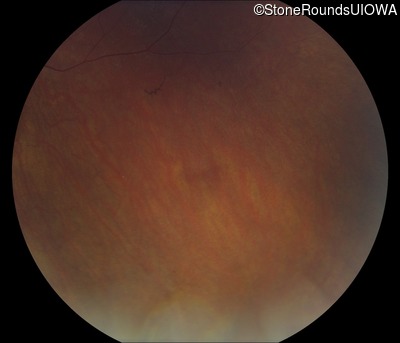

Fundus Photography - Right - 5/180

Exemplar